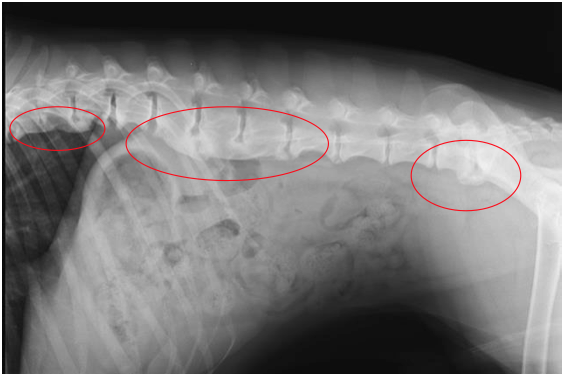

Spondylosis Deformans

Discospondylitis